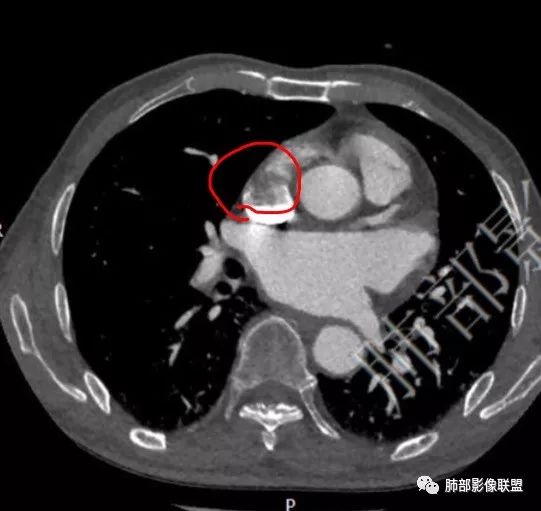

定位右心房。 医学百科网 | YxBaike.Com

右房占位,向上腔静脉侵犯。 医学百科网 | YxBaike.Com

右房游离壁。

向腔外明显突出,形态不规整,恶性? 医学百科网 | YxBaike.Com

不规则。 医学百科网 | YxBaike.Com

周围结构有没有受累或受压?上腔静脉口是不是受累?

受累。

李宇:这个明显长进去的。 医学百科网 | YxBaike.Com

上腔静脉受累了就考虑血管肉瘤啦。 医学百科网 | YxBaike.Com

心包有增厚积液,心包也有累及。 医学百科网 | YxBaike.Com

心包少量积液。 医学百科网 | YxBaike.Com

心包左侧是不是有壁结节,增厚是有的。

心包不规则增厚。 医学百科网 | YxBaike.Com

心脏血管肉瘤可分为腔内型及向心包弥漫性浸润型,其中腔内型可呈单发或多发大小不等、不光滑的向腔内生长为主、宽基底的低密度结节状或团块状占位,发现时一般瘤体较大,常分叶,并向邻近组织结构膨胀性生长,挤压或侵犯相邻组织或冠状动脉;而向心包弥漫性浸润型血管肉瘤主要向心包浸润,引起心包增厚与积液。

(右心房肿物)高级别血管肉瘤,浸润心肌组织。

血管肉瘤是最常见的心脏原发恶性肿瘤,最好发的位置在右房游离壁,病变容易局部增长累及冠状动脉、心包、三尖瓣等,心包积液比较常见,高级别的血管分化好,增强后不均匀明显强化。低级别血管分化差,强化弱,肿瘤细胞容易脱落入血肺内、全身多处转移,转移病灶容易出血。